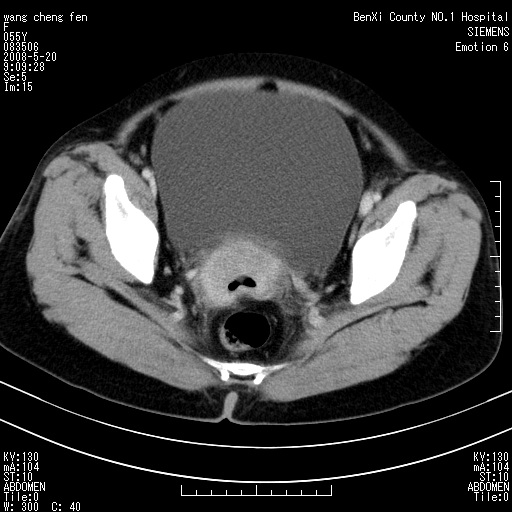

女、绝经后阴道流血3个月

左侧附件区巨大囊实性病灶,边缘光整,病灶囊壁较厚,增强示囊壁及实性部分明显强化,强化呈度与宫体实质大致相同,宫腔积液征像,未见盆腔积液等其他异常,考虑左侧卵巢囊腺癌,不除外囊腺瘤及浆膜下肌瘤坏死

左侧附件区巨大囊实性病灶,边缘光整,病灶囊壁较厚,增强示囊壁及实性部分明显强化,强化呈度与宫体实质大致相同,宫腔积液征像,未见盆腔积液等其他异常。绝经后阴道流血3个月,结合病史左侧卵巢囊腺癌首先考虑,宫腔扩大不除外累及。期待结果。

支持浆膜下子宫肌瘤.之前由于网络原因未看全图片,现在重看,宫颈见一类圆形低密度影,增强轻度强化,低于肌层强化,宫腔扩大,考虑宫颈癌伴宫腔积液可能性大.

囊实性肿块分隔厚度较大,厚薄不均,增强实性成分明显强化,有不规则阴道流血,卵巢囊腺癌可能性大。

1,宫颈部占位,宫颈癌?2,左侧附件区囊实性占位,界较清,实质部分强化明显。考虑浆膜下或阔韧带肌瘤囊变可能大。囊腺类肿瘤不除外。